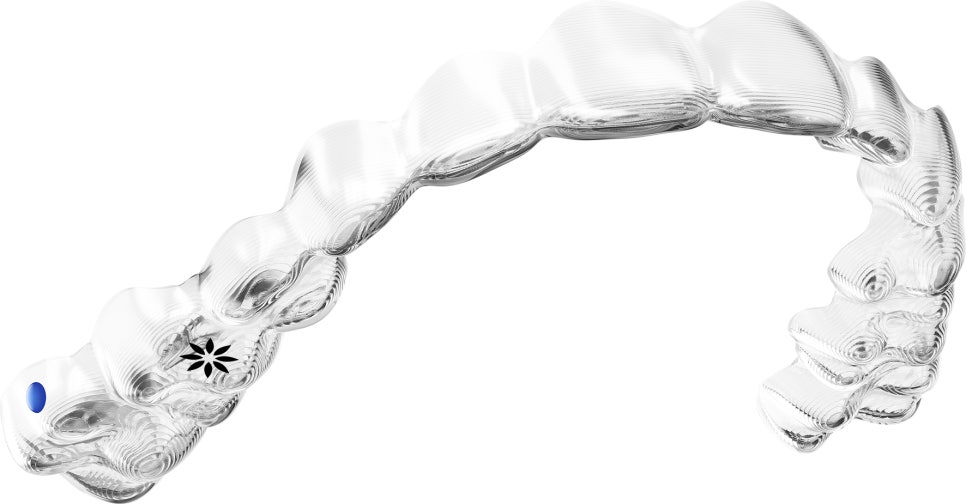

인비절라인이란 ??

특수 강화 플라스틱으로 된 틀을 이용하여

치아를 교정하는 시술 입니다.

두께가 0.75mm 정도 라고 하니

입안에서도 이물감이 적겠죠??

또한,

눈에 띄지 않아 심미적이고

탈부착이 가능하며

처음부터 끝까지

교정장치가 나와있어

군대에 가시거나, 유학, 출장 등

잦은 내원이 힘드신 경우에도

적합한 교정장치 입니다.